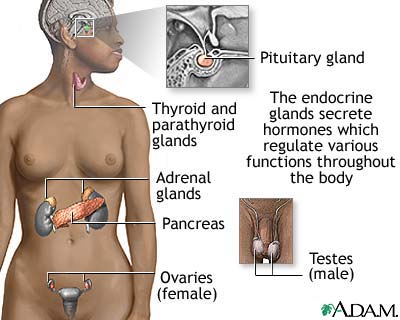

The pancreas is an organ located behind the stomach. It produces the hormones insulin and glucagon. It also produces chemicals called enzymes needed to digest food.